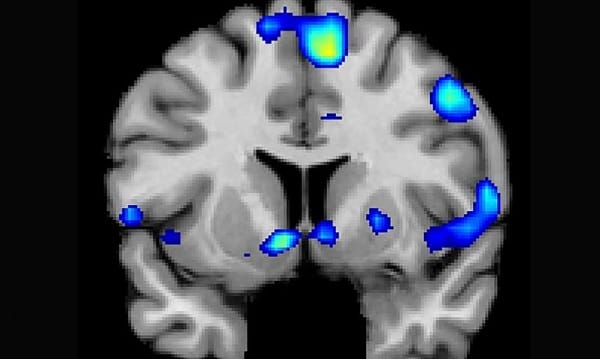

圖為實驗中受試者的大腦功能性磁振造影圖像,研究人員發現受試者在接觸到宗教信仰時,腦部掌管獎賞和成癮的部位會有反應。

而在此過程中,研究團隊發現,宗教信仰能夠讓參與者腦部的伏隔核(nucleus accumben)產生可再生的刺激,而其中伏隔核就是能讓人類感受到獎賞、快樂、笑、成癮、侵犯、恐懼以及安慰劑等效果的大腦部位。此外,他們也發現大腦中掌控專心程度、新奇與重要事情理解力的部位也會在此過程中受到刺激。